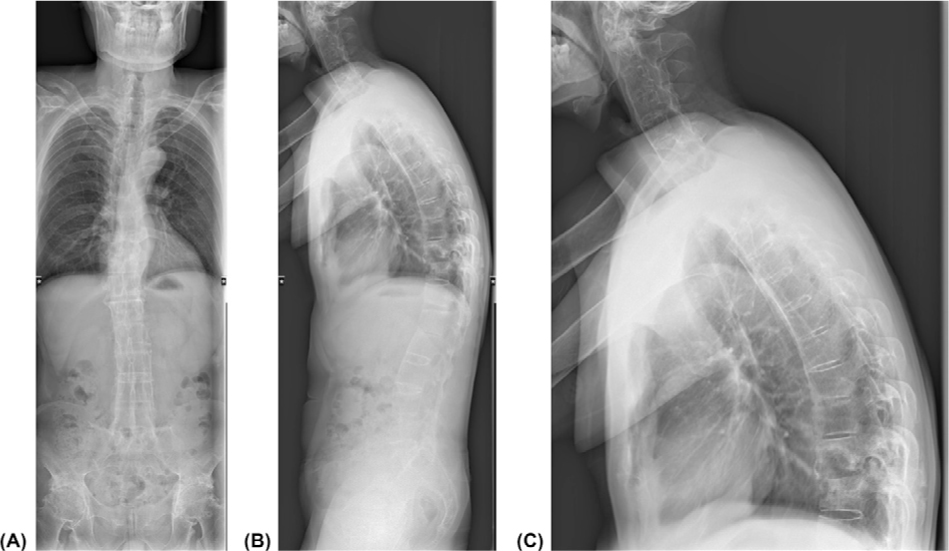

A 50-year-old male was admitted to our hospital due to “recurrent back pain for 18 years, aggravated with numbness and weakness of the right lower limb for 3 months.” After admission, his physical examination showed that his spine activity was significantly limited. His HLA-B27 test was positive, and X-ray showed that his bilateral sacroiliac joint space had disappeared, hip joints were narrowed and femoral head was necrotized (Figure 1). Bone destruction was observed on the lower edge of T10 vertebral body and the upper edge of T11 vertebral body. Subsequent biopsy result revealed that the damage was not caused by tumor or infection. The patient was diagnosed as Ankylosing Spondylitis (AS) with Andersson lesion (AL). AL is a rare complication of AS, first described by Andersson in 1937.[1, 2] AL is a lesion of the intervertebral disk–vertebral interface at the late stage of AS, which can be characterized as a combination of bone hyperplasia and bone destruction. AL can be easily misdiagnosed as an infectious disease (such as spinal tuberculosis) or a neoplastic disease in clinical practice. The patient adopted surgical treatment and underwent standardized tumor necrosis factor antagonist (Etanercept) treatment after operation. So far, the patient's pain and numbness of right lower limbs have significantly reduced.

Full spine X-ray showed the patient's spinal changes. From the full spine X-ray, thoracic kyphotic deformity and bamboo-like changes in the thoracolumbar spine were observed. The lower edge of T10 vertebral body and the upper edge of T11 vertebral body showed bone destruction. The structure of attachment area bone was disordered and the density was uneven. The bilateral sacroiliac joint space had disappeared, the bilateral hip joints were narrowed and bilateral femoral head was necrotized. (A) Full Spine X-ray (PA); (B) Full Spine X-ray(LAT); (C) T-Spine X-ray (LAT).